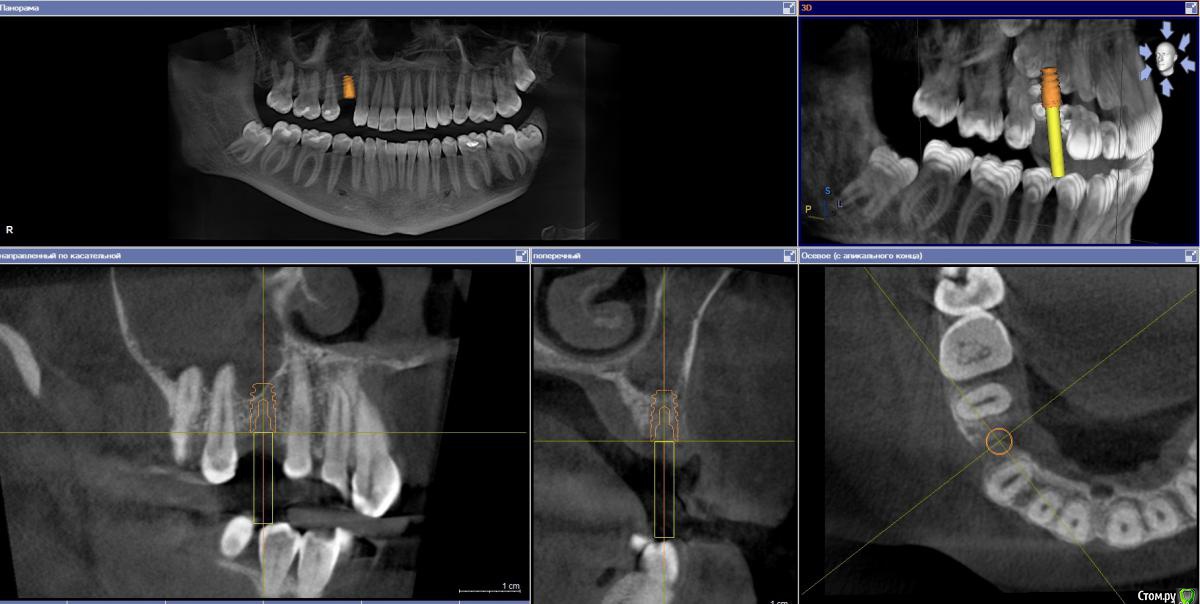

Ponchik Опубликовано 1 августа, 2017 Автор Поделиться Опубликовано 1 августа, 2017 Так и не состоялся тот случай, но сразу же пришла другая пациентка с подобной проблемой. (Проблема в докторе не делающем синус-лифтинга)Планирование Что получилось сразу Формирователь через 3 месяца Ставил AB SPI 4.2 - 8 Фрезой до 6мм, далее вогнутым остеотомом. Изменений в звуке не заметил. Достучал до ограничителя и все.Что в пазухе проблемы увидел, только потом на КТ после имплантации.Всё.Кидайте тапками.P.S.Это был первый имплант на верхней челюсти. Ссылка на комментарий

kamranchick Опубликовано 1 августа, 2017 Поделиться Опубликовано 1 августа, 2017 Так и не состоялся тот случай, но сразу же пришла другая пациентка с подобной проблемой. (Проблема в докторе не делающем синус-лифтинга)Планированиедо.jpg Что получилось сразупосле.jpg Формирователь через 3 месяца 3ме.jpg3мес.jpg Ставил AB SPI 4.2 - 8 Фрезой до 6мм, далее вогнутым остеотомом. Изменений в звуке не заметил. Достучал до ограничителя и все.Что в пазухе проблемы увидел, только потом на КТ после имплантации.Всё.Кидайте тапками.P.S.Это был первый имплант на верхней челюсти.если жалоб нет то все ок Ссылка на комментарий